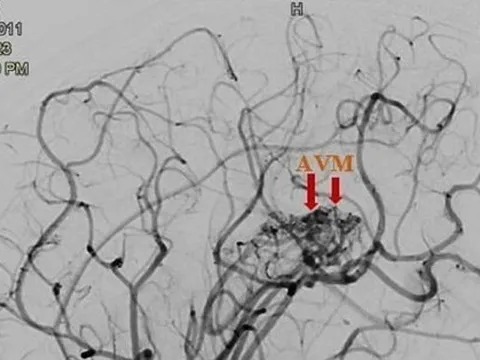

Bé gái 12 tuổi bị đột quỵ

Cho rằng con học nhiều nên bị đau đầu gia đình không đưa đến bệnh viện thăm khám, hơn 1 tháng sau bé gái 12 tuổi rơi vào tình trạng yếu nửa người bên trái. Tại bệnh viện, bác sĩ xác định trẻ bị đột quỵ do vỡ dị dạng mạch máu não.